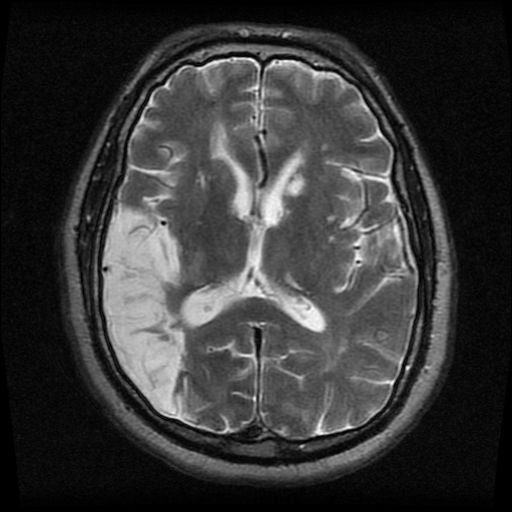

The rare symptoms of parietal stroke are: - Gerstmann Syndrome It is a sensory disorder characterized by inability to write, do calculations and identify fingers as well as left-right disorientation. - Apraxia Since stroke in the parietal lobe can interfere with the executive functioning, the individual suffering from parietal stroke can develop motor apraxia, constructional apraxia, ideomotor apraxia, and eye-opening ataxia. Reference: https://www.verywellhealth.com/effects-of-a-parietal-lobe-stroke-3146435#common-symptoms Image via: https://dizziness-and-balance.com/testing/ENG/cases/parietal%20lobe/case1.html